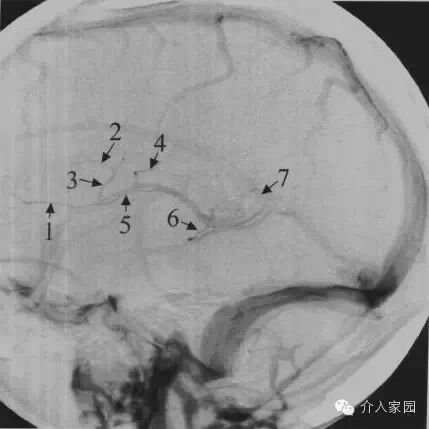

1、上矢狀竇 2、橫竇 3、乙狀竇 4、中央溝靜脈

5、上吻合靜脈 6、丘紋靜脈 7、靜脈角 8、基底靜脈